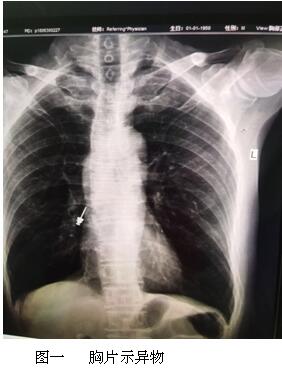

六月最后一天的上午,內(nèi)鏡中心來了一名特殊的患者,患者表情焦慮,訴于外院補(bǔ)牙時(shí),不小心把補(bǔ)牙的一顆螺絲吞下,現(xiàn)咽喉部明顯不適,于我院耳鼻喉行喉鏡檢查,未見明顯異物,內(nèi)鏡中心伍友興主任聽聞后,考慮異物可能卡在食管上段,持鏡給予患者行胃鏡檢查,但是反復(fù)觀察食道、胃及十二指腸,并未找到患者所描述的異物。是不是有可能異物已經(jīng)掉入十二指腸以下的消化道了呢?如果已經(jīng)掉入小腸,這一顆大約長2cm的螺絲,表面無明顯銳利邊緣,刺破腸管的可能性較小,可自行隨大便排出,正當(dāng)我們準(zhǔn)備松一口氣告訴患者胃鏡下未見明顯異物時(shí),患者輕輕的咳嗽兩聲引起了伍主任的注意,“快去行胸部照片,異物可能掉入氣管”伍主任說到,患者遂行胸部照片,見異物果然出現(xiàn)在患者右側(cè)的肺里,為進(jìn)一步確定異物部位,給予行胸部CT檢查,并積極聯(lián)系呼吸內(nèi)科豐偉民主任,黃雪英老師與豐主任兩人密切配合,在支氣管鏡下看到右側(cè)支氣管下段,找到了讓人揪心的異物,順利取出,此刻患者緊縮的眉頭終于舒展開來,連連向我們醫(yī)務(wù)人員道謝。